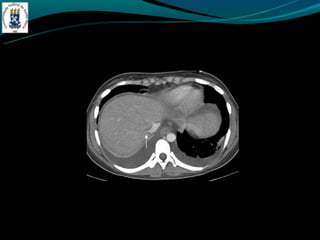

- TC: hepatomegalia heterogênea, não visualização das veias

hepática, ascite, realce hepático central, lobo caudado preservado

BUDD-CHIARI -Hipercoagulabilidade -Compressão – tumor -Membranada VCI -Dor abdominal, hepatomegalia e ascite. - TC: hepatomegalia heterogênea, não visualização das veias hepática, ascite, realce hepático central, lobo caudado preservado ou aumentado.